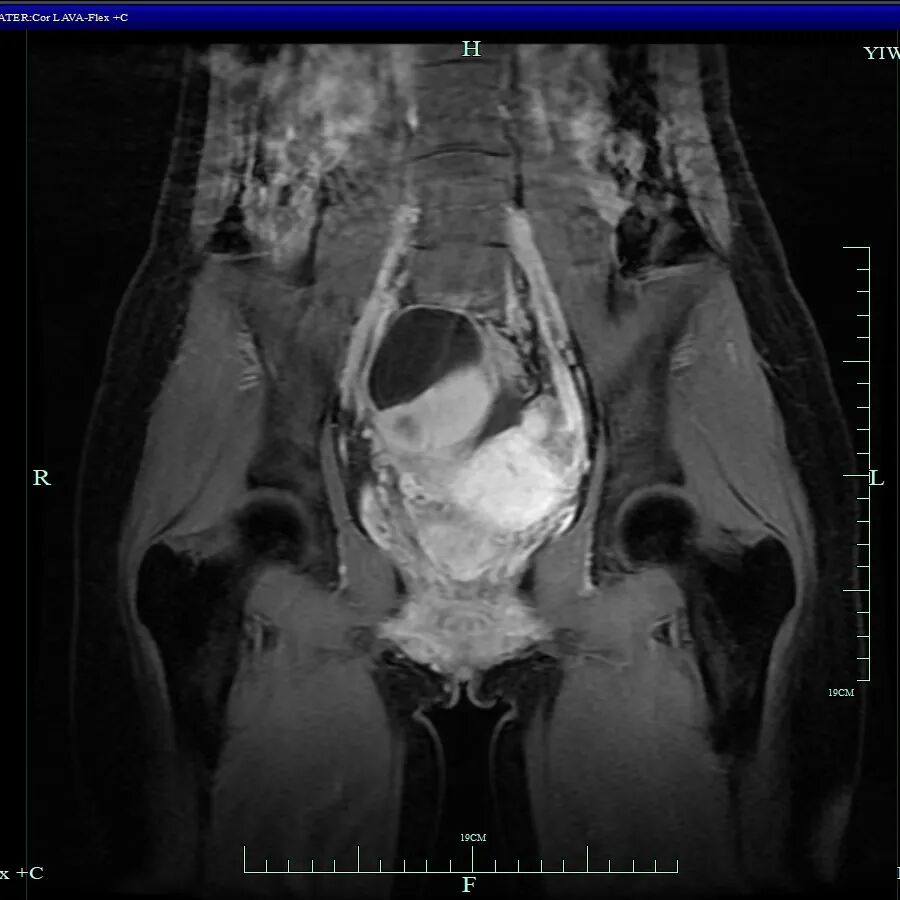

经过紧急CT检查,结果显示小杨的盆腔偏右侧存在一个不明占位。这个结果如同一记警钟,她被迅速转入妇科进一步诊治。

妇科主任吴萍为其详细检查后,诊断为卵巢子宫内膜异位囊肿、子宫内膜异位症四期(重度)、子宫腺肌病、肠道子宫内膜异位症

术中发现其盆腔内器官广泛严重粘连,右侧卵巢有直径约10厘米的囊肿,左侧卵巢亦有囊肿,并在直肠前壁等多处发现异位病灶。手术团队凭借精湛技术成功分离粘连,精准切除了所有病灶,并修复受损组织,保住了生育器官,手术圆满完成。